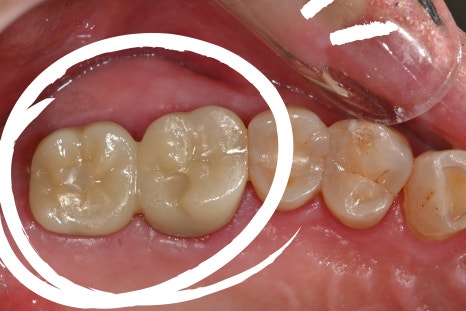

The final stage of an implant is the prosthesis (crown).

It is the stage where the visible tooth shape is completed, but in reality, it involves some of the most delicate work.

Fit between the gums and the prosthesis

Harmony of height and width with the surrounding teeth

This patient tended to have a bite that leaned to one side, so in the prosthetic stage of the implant treatment, we designed it to distribute that force as much as possible.

It was custom-made at the in-house dental lab based on scan data, and after placement, photographs were used to check the fit between the gums and the prosthesis again.